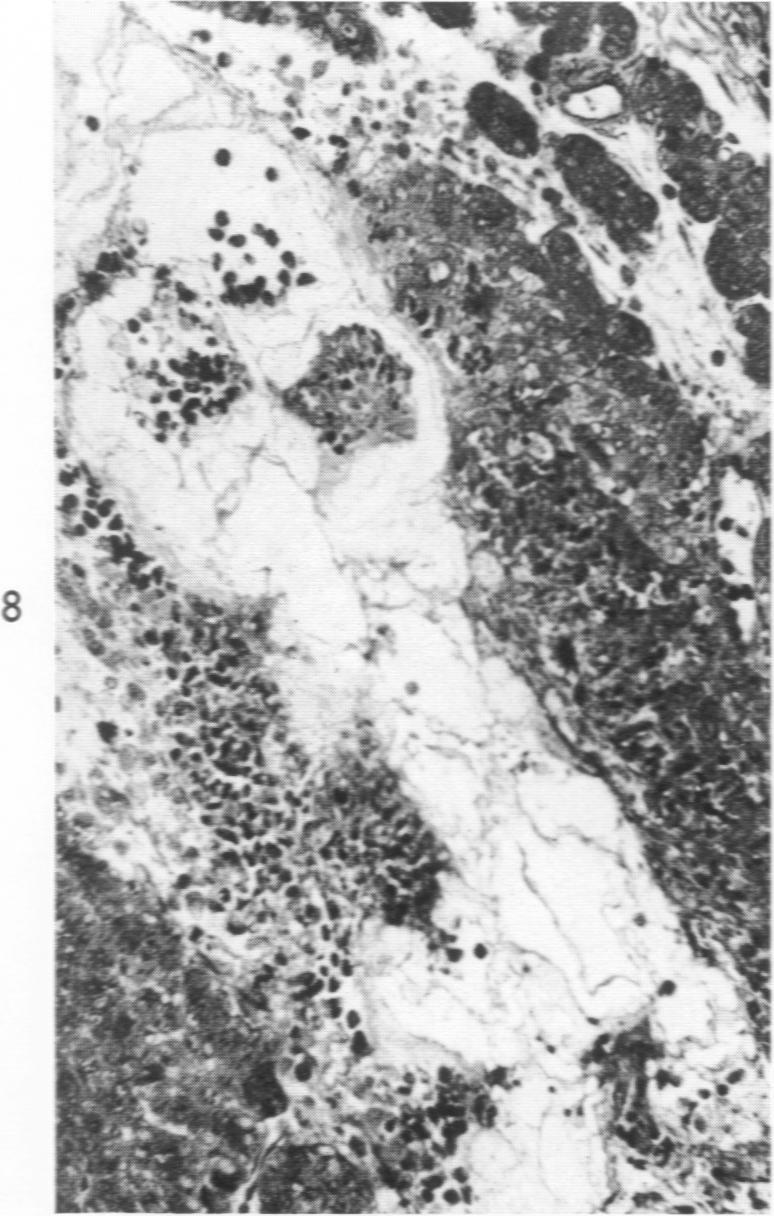

Volk B W, Lazarus S S

Am J Pathol. 1960 Aug;37(2):121-35.